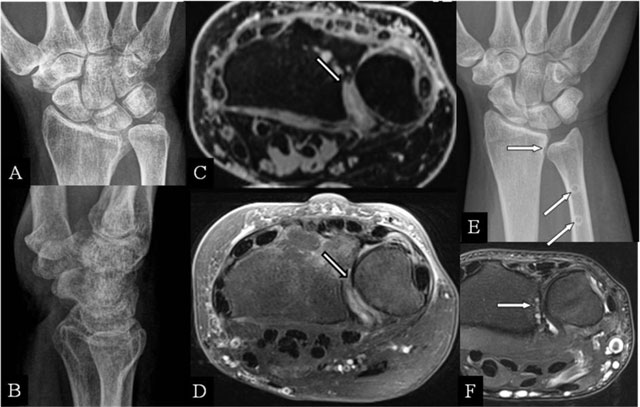

Figure 2

Radioulnar abutment and ulnar impingement. (A, B) PA and lateral plain radiographs; (C) Axial 3D-GRE; (D) SE T2-WI FS; (E) PA plain radiograph; and (F) Axial SE T2-WI FS. (A, B) Sequelae of a Pouteau-Colles fracture of the distal radial epiphysis. (C) Residual step-off at the radial sigmoid notch. (D) Destruction of the cartilage at the dorsal part of the sigmoid notch. (E) Excessive shortening (horizontal arrow) after surgery (oblique arrows). (F) subchondral erosions at the most proximal part of the radial sigmoid notch.